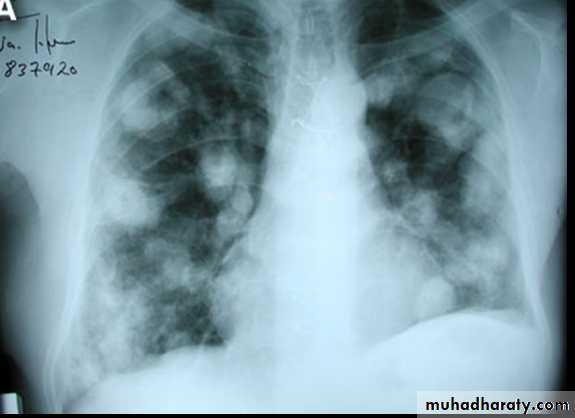

CXR With multiple H.cysts

cestodes